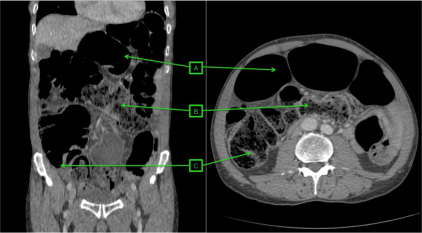

El diagnóstico actual de la se realiza mediante TC abdominal:

- El hallazgo patognomónico es el signo de la escarapela o diana identificable en la TC o ecografía.

- Podemos ver la imagen de “Intestino dentro de intestino” gracias a las reconstrucciones multiplanares.